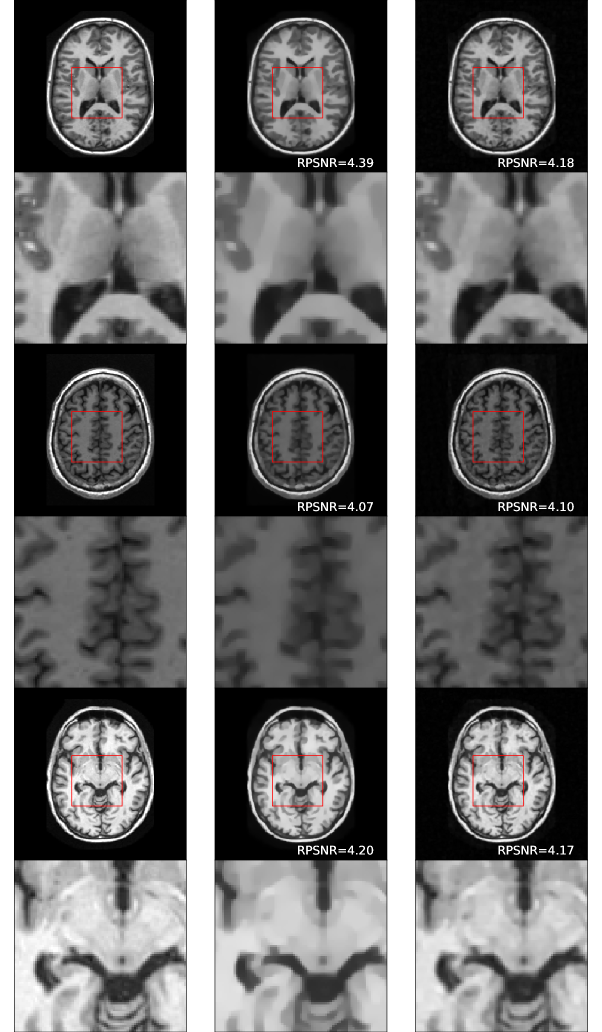

Fig. 5 shows some example reconstructions computed by the DHS large model. Along each row, we selected two reconstructions for the corresponding ground truth by collecting the subset of images within RPSNR range [4,4.5]44.5[4,4.5] and finding the two which had maximum distance in terms of 2subscript2\ell_{2}. In particular, we observe the varying levels of smoothness and sharp detail for a single slice despite the fact that the overall quality of the reconstructions (as measured by RPSNR) is virtually indistinguishable.

Refer to caption

Figure 5: Example slices, full-size and zoomed-in. First column are full-resolution images. Subsequent columns are reconstructions with similar RPSNR but computed with different regularization weights.